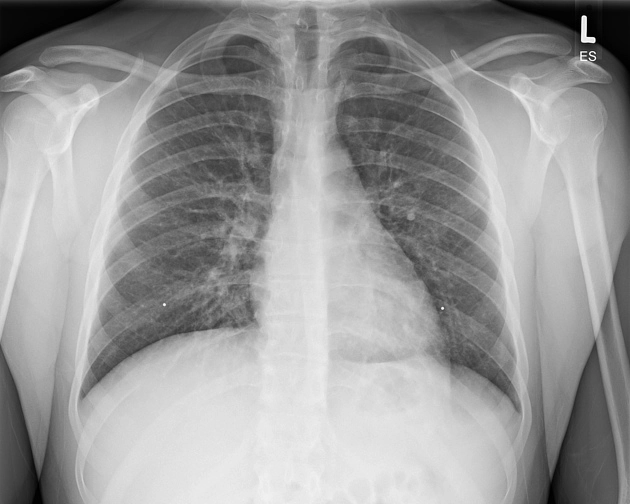

Tổn thương phổi liên quan đến sử dụng thuốc lá điện tử hoặc sản phẩm vaping (E-cigarette or vaping product use-associated lung injury - EVALI)